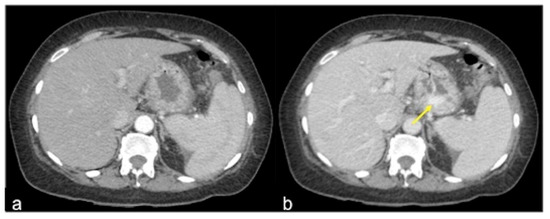

| Colorectal Cancer/Polyps (Figure 6, Figure 36, Figure 37 and Figure 38) | Bowel obstruction with or without bleeding. | Adenocarcinoma: irregular wall thickening with or without stenosis [25]; Polyps: mass-forming protrusions in the intestinal lumen with vascularised peduncle. |

- Iacobellis, F.; Perillo, A.; Iadevito, I.; Tanga, M.; Romano, L.; Grassi, R.; Nicola, R.; Scaglione, M. Imaging of Oncologic Emergencies. Semin. Ultrasound CT MRI 2018, 39, 151–166. [Google Scholar] [CrossRef]